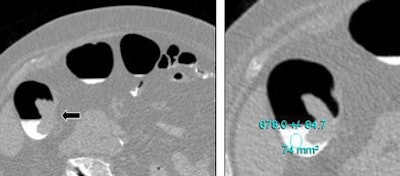

| Above, tagged fluid surrounds a malignant tumor (arrow). The tagged fluid has a density of 678 HU. Images courtesy of Dr. Philippe Lefere. |

The biggest difference was seen in group 3, which received a final dose of 25 mL of 4% barium solution on the morning of the exam. Most parameters were similar to those in Group 1, except that just 3.3% of segments had untagged fluid, representing a major improvement in fluid tagging.